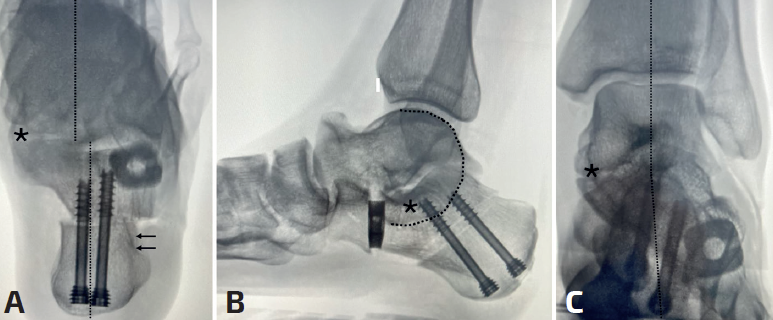

mact.1701.fs2403006-figura2.png

Figura 2. Doble osteotomía del calcáneo (alargamiento dela columna externa con cuña de metal trabecular + deslizamiento medial) en caso de coalición talocalcánea fibrosa con deformidad en valgo y abducto. A: corrección en la proyección axial de Harris intraoperatoria (observar la alineación tibiocalcánea); B: proyección lateral en carga simulada intraopertaoria (en este caso sí que mejoró la relación talocalcánea); C: anteroposterior del tobillo en carga simulada intraoperatoria (adecuada relación tibiotalocalcánea, obsérvese la apertura del espacio lateral subfibular). Líneas discontinuas: alineación intraoperatoria. Línea discontinua curva: signo de C; asterisco: área de coalición.

Si ambas deformidades están presentes en un grado acusado o si al corregir una de ellas se observa una deformidad residual importante, la elección será combinar ambos tipos de osteotomías (Figura 2). Seguimos los mismos criterios de apertura que en el pie plano flexible, intentando no sobrepasar los 8 mm en adultos para evitar problemas en la calcaneocuboidea(10). En caso de persistir el valgo tras esta osteotomía o si para corregir necesitamos abrir una cuña de más de 1 cm, optaremos por realizar una doble osteotomía, añadiendo una traslación medial del calcáneo.